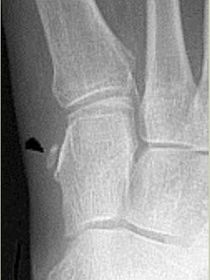

| Describe the alignment of metatarsal 2 | There is no angulation nor displacement of the distal segment relative to the proximal segment. |

| Describe the alignment of metatarsal 3 | The distal segment is displaced laterally (50% apposition) and angulated medially. |

| Describe the alignment of metatarsal 4 | The distal segment is displaced laterally (75% apposition) but there is no apparent angulation. |

| Describe the tubulation of the metatarsals | Metatarsals are overtubulated - decreased girth. |

| Describe the tubulation of the metatarsals | Metatarsals are undertubulated - increased girth. |